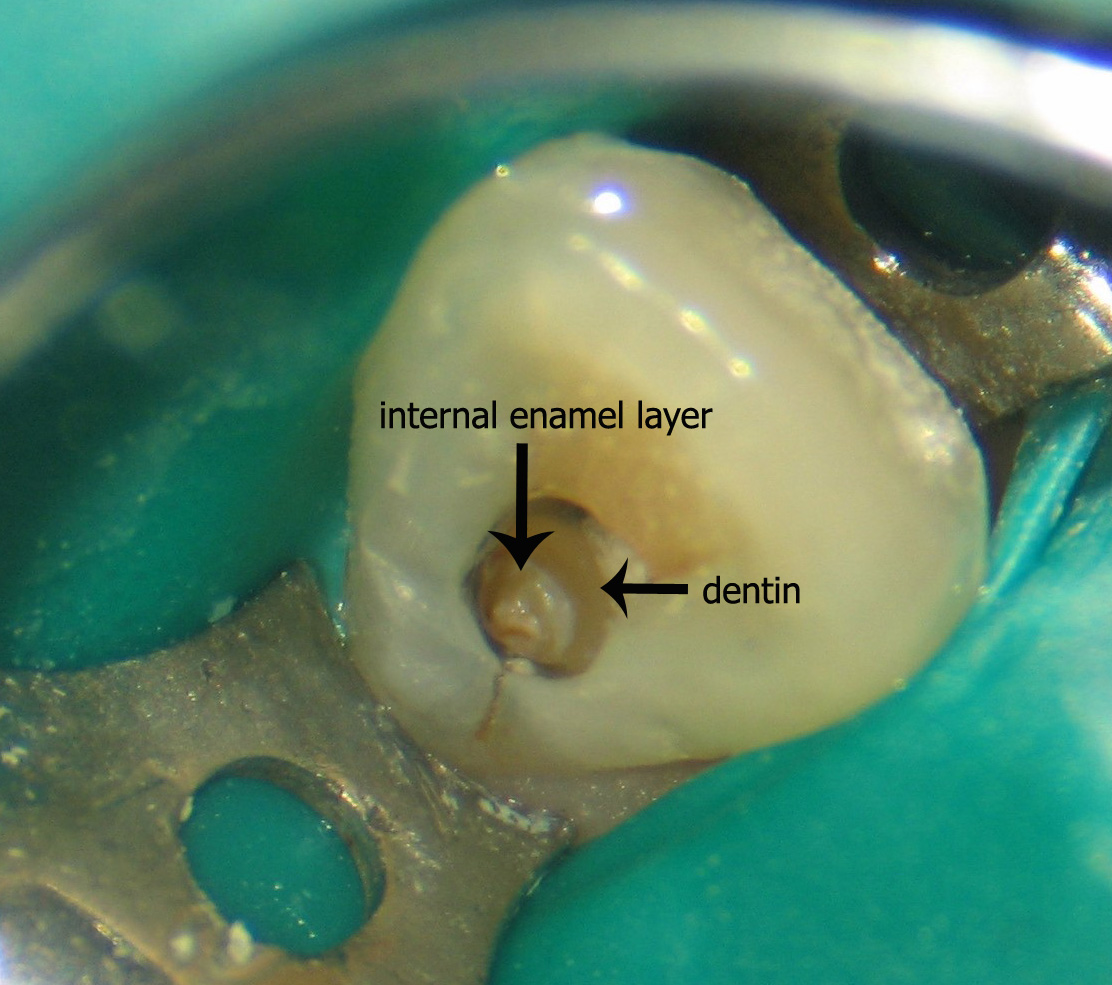

Dens in dente

Subtema

Tiene su origen en el plegamiento de la superficie coronaria de un diente antes de que se produzca su calcificación.

Dens evaginatus

Tiene su origen en el plegamiento de la superficie coronaria de un diente antes de que se produzca su calcificación.